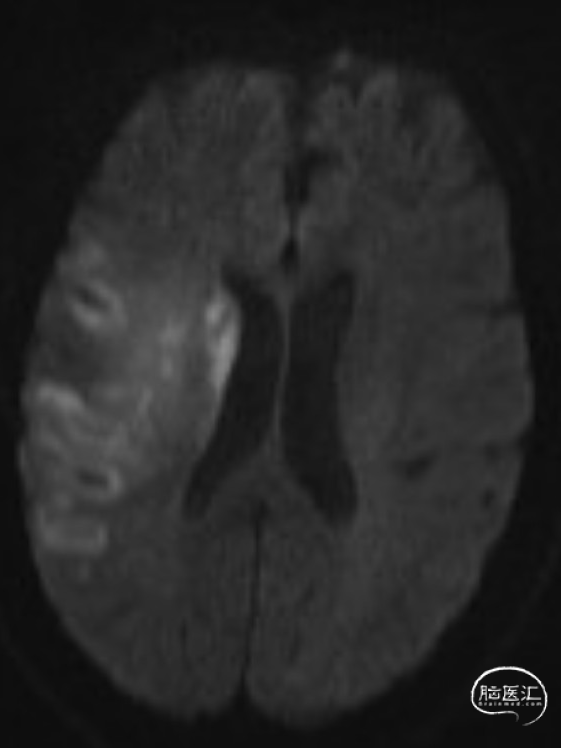

查头颅MRI:右侧基底节区、右侧顶颞岛叶急性脑梗死。